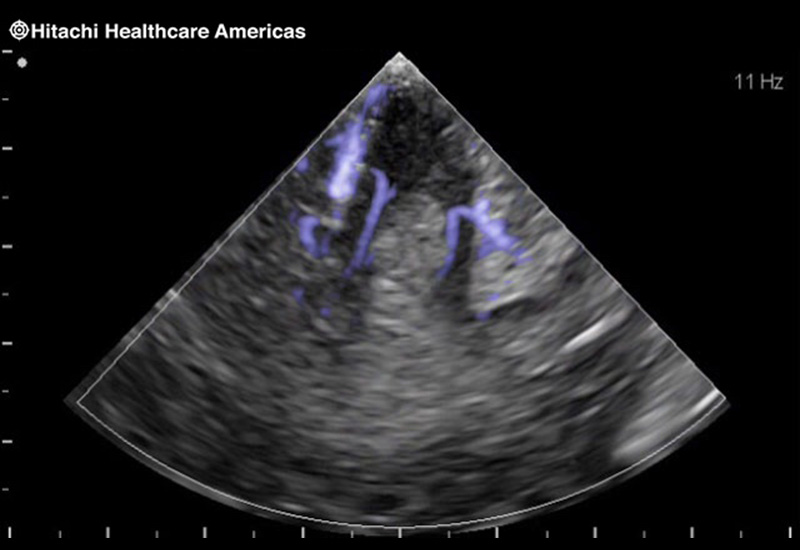

Giving the surgeon complete control

The Fujifilm Healthcare transducer utilizes the full benefits of the Wrist Articulation™ of the robotic instruments to capture real-time ultrasound imaging even at complex angles and difficult-to-reach areas.

Our smallest footprint allows for enhanced contact in tight spaces

Our newest probe, the L51K allows the surgeon access to difficult-to-reach areas that no other probe on the market can go. The unique design and proximal location of the attaching mechanism provides full wrist articulation and easier grasp and release.

The next level in Robotic Ultrasound

Full wrist articulation with optimized functional length.

A critical function of robotic ultrasound guidance is tumor margin identification. Fujifilm's family of robotic probes all have the optimum location of the attaching mechanism that allows for full wrist articulation of the probe. The result is an increased confidence that the tumor margins have been completely identified.